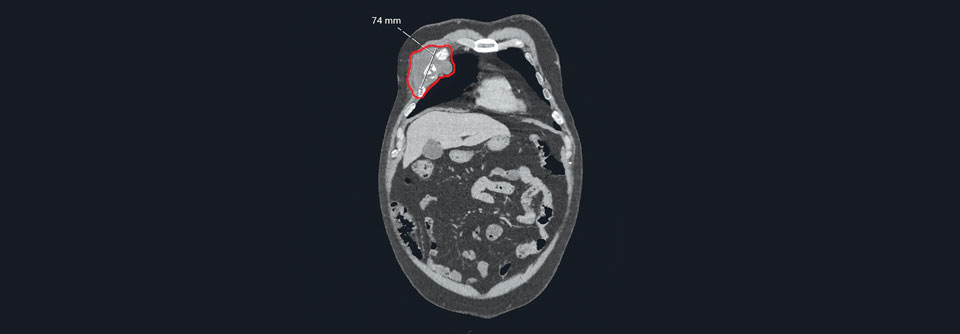

Durch molekulargenetische Verfahren lassen sich einige Sarkome von den mehr als 70 bekannten Subtypen unterscheiden. Durch molekulargenetische Verfahren lassen sich einige Sarkome von den mehr als 70 bekannten Subtypen unterscheiden. © ipopba– stock.adobe.com